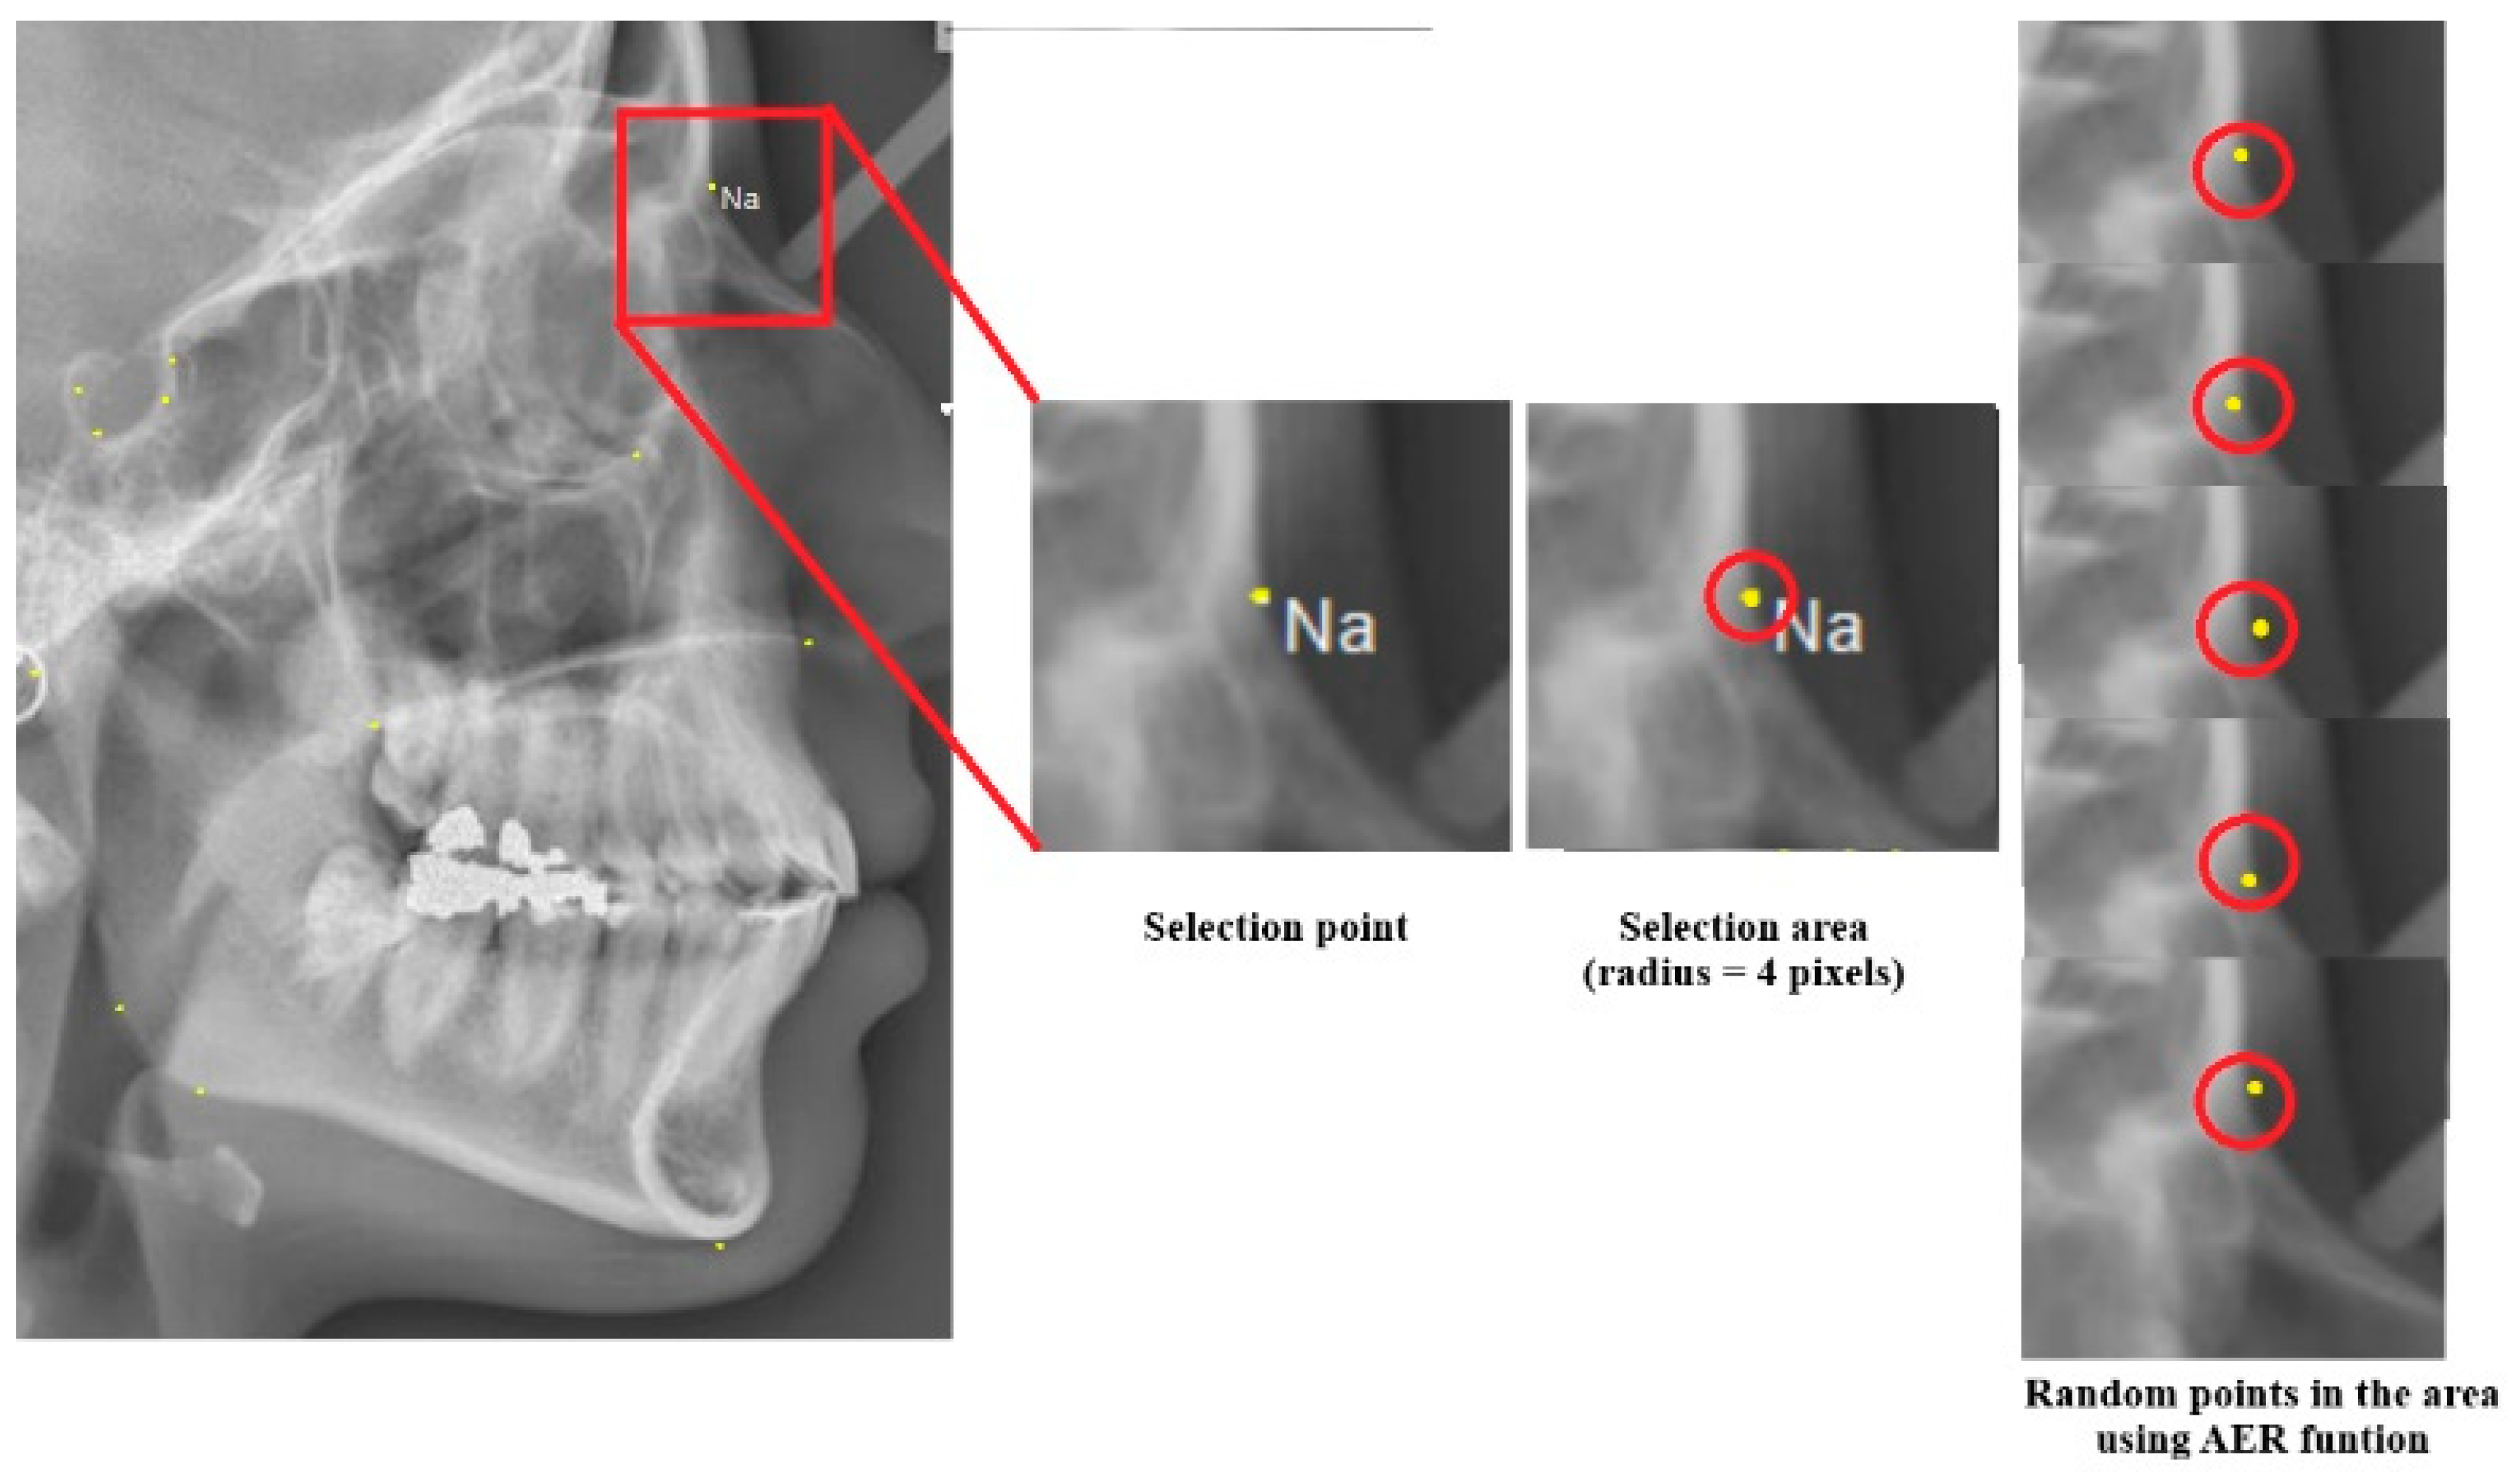

It is reported that acceptable accuracy levels for cephalometric landmark selection are 0.59 mm (x coordinate) and 0.56 mm (y coordinate) in total error for diagnostic purposes [48]. Additionally, the reported radius area for the selection landmarks in previous studies was about 2 mm [49]. The Auto Error Reduction (AER) function is designed to minimize user-induced errors in the algorithm. It addresses potential discrepancies between landmarks identified in the PM cephalogram and those in the AM cephalogram of the same individual. Initially, the user selects landmark points from the AM cephalogram, and the algorithm processes these points to encode the individual’s identity in the database. If the same individual later becomes a victim, their PM cephalogram is imported into the software and analyzed by either the same or a different orthodontist. The AER function helps minimize the impact of user errors during the victim analysis phase. If a case in the database shows high similarity but less than 100%, it indicates that the algorithm likely identified the victim correctly. However, the similarity score may fall short of 100% due to potential user errors and variations in landmark selection between the AM and PM radiographs.

In the AER function, a region of interest with a radius of 4 pixels is considered around each key landmark point, rather than focusing on a single point (Figure 4). This approach accounts for the potential variation in landmark placement.

Figure 4.

The AER function can generate random points within the landmark area (red circle). This process is applied to the key landmarks to account for potential variations.

In the AER function, random points are generated within the landmark area, with a default radius of 4 pixels. The algorithm is executed for each set of points to compute the similarity. If the similarity improves, the updated landmark points are stored, and the process continues until the similarity reaches its maximum value. This iterative process is repeated between 100 and 1000 times by default, allowing for potential improvements in the similarity percentage. The radius of the landmark area can be adjusted by the user.